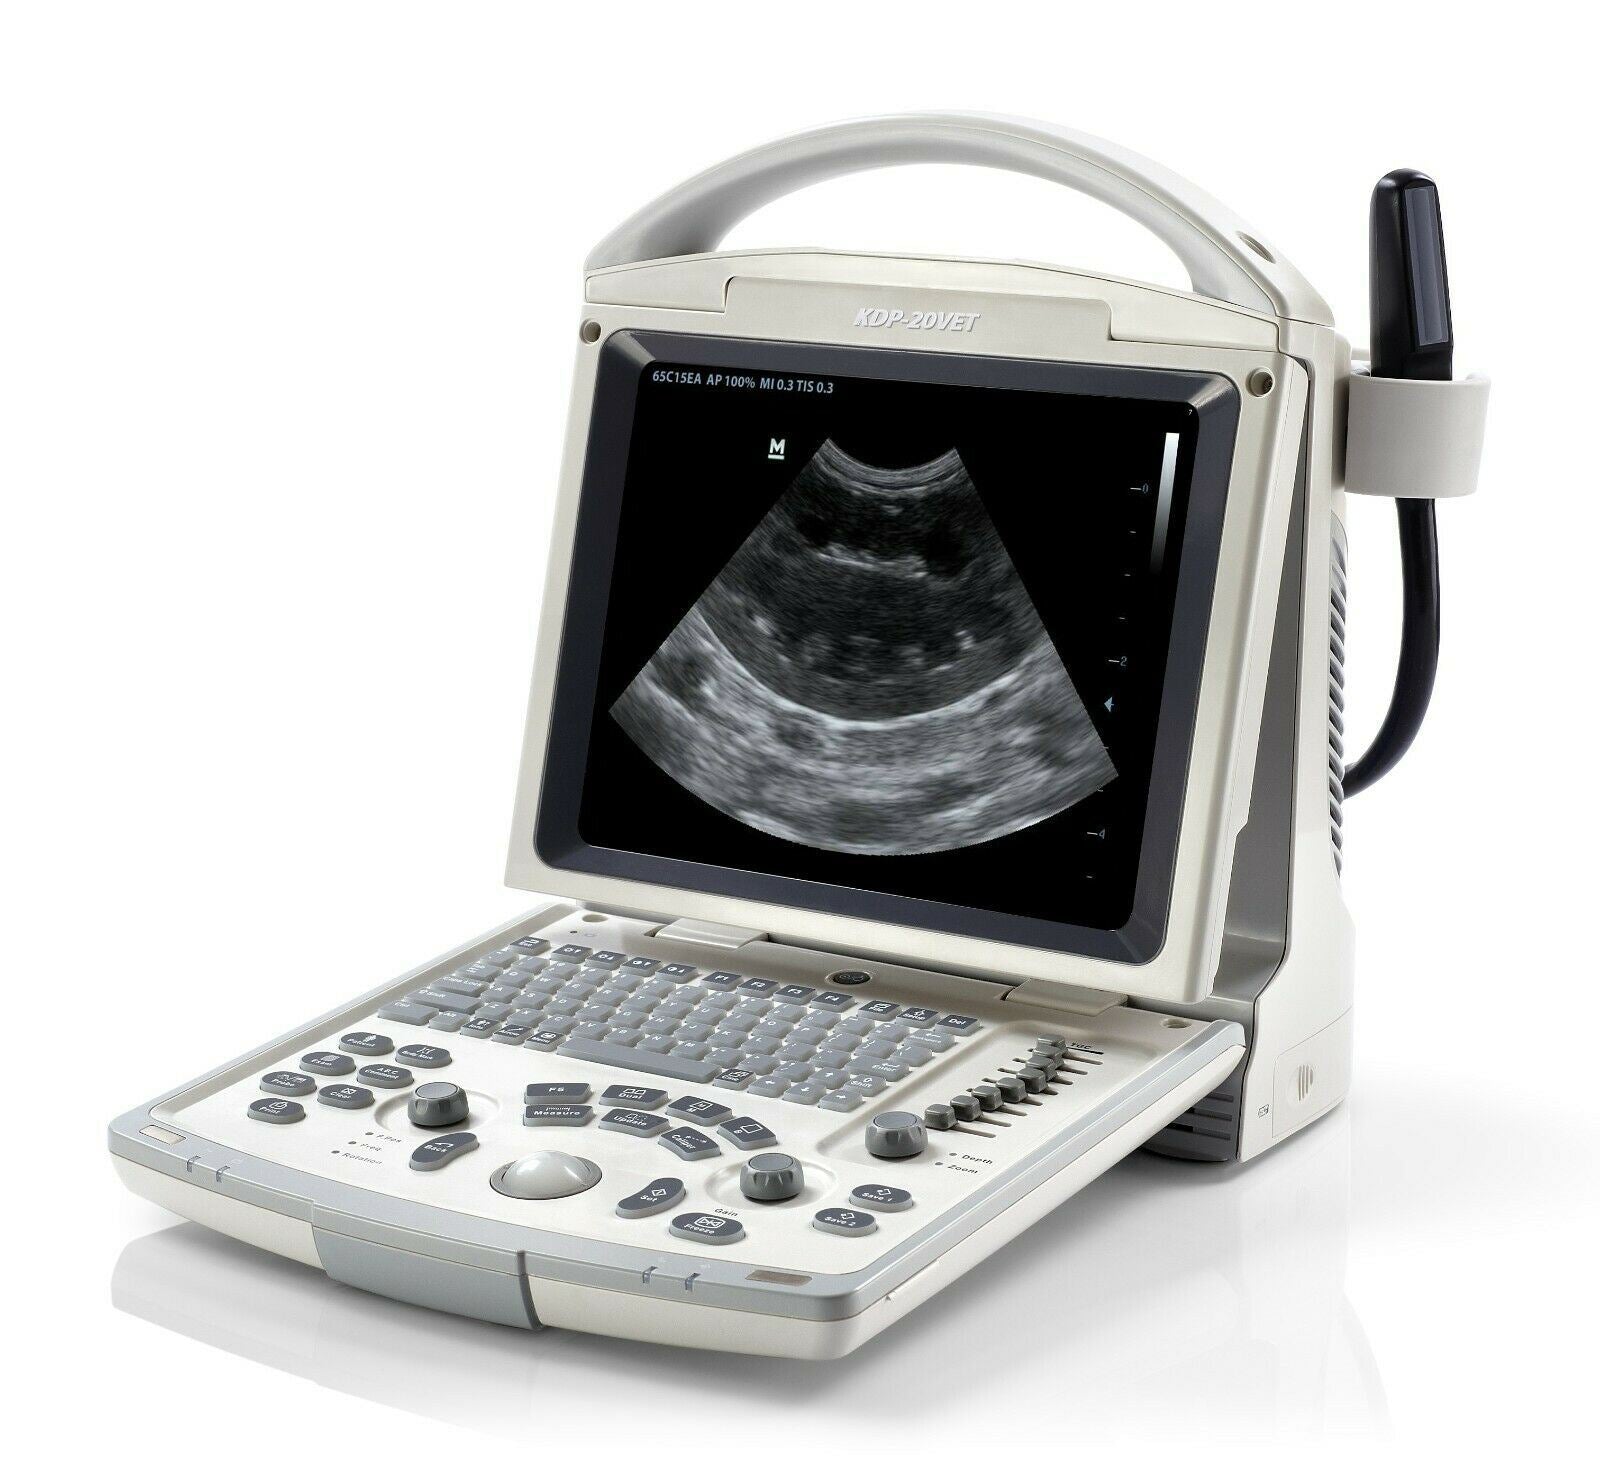

Veterinary Ultrasound K-DP-20Vet

- With 3 Probes

Keebomed K-DP-20 is equipped with a best-in-class combination of performance and affordability. Provides the latest imaging technologies and convenient workflow options. Offers abundant measurement packages covering traditional ultrasound applications and emerging fields such as urology, MSK, and anesthesia.

- High resolution 12.1” LED with tilt functionality